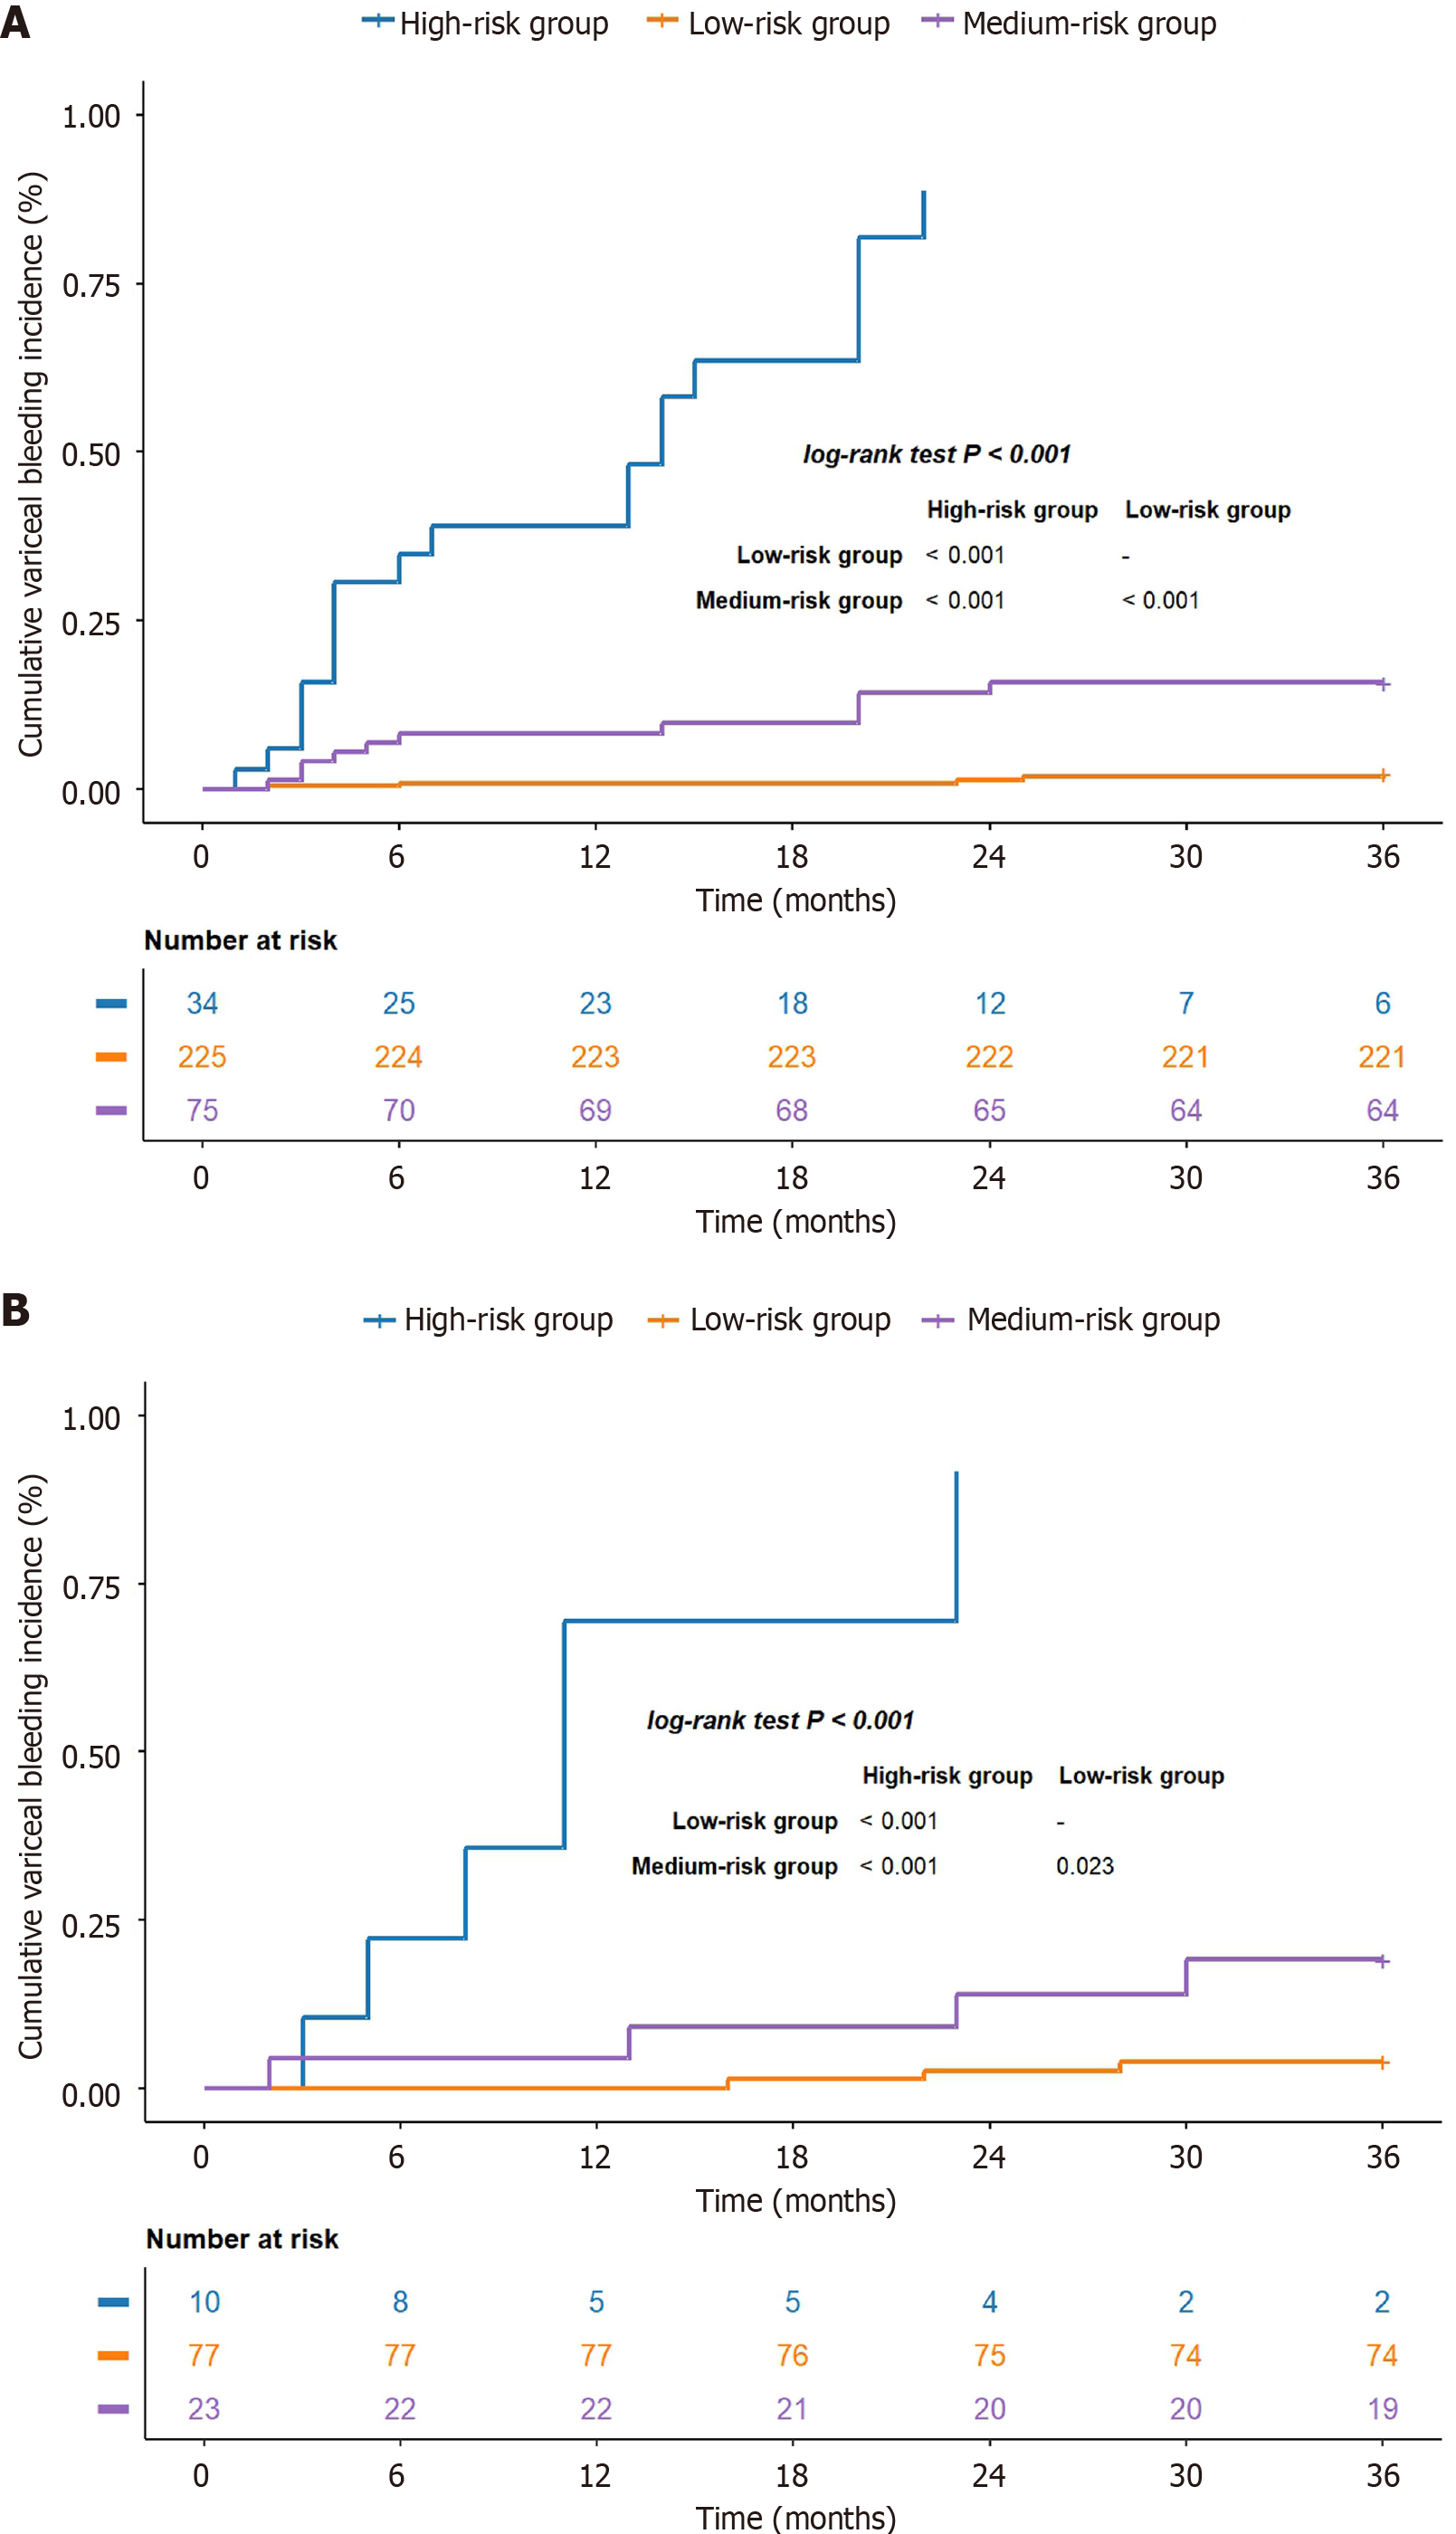

According to the R + C model, the risk analysis was performed for individuals diagnosed with BCS complicated by GEVs. The relevant equation was as follows: Risk assessment = 0.847 Sex - 0.008 platelet count - 2.417 invasive treatment to relieve hepatic venous outflow obstruction + 2.366 use of anticoagulant medication + 0.435 Radscore. The specific threshold was identified through X-tile, and all participants were classified into low-, moderate- or high-risk categories according to their likelihood of bleeding (low risk: < 0.57; medium risk: 0.57-1.11; high risk: > 1.11). In the training set, the cumulative occurrence rates of variceal hemorrhage were 2.2%, 14.7% and 85.3% for the low-, moderate- and high-risk groups, respectively (log-rank test, P < 0.001; Figure 8A). Within the validation group, the cumulative incidence rates were 3.9%, 17.4% and 90% for each group (log-rank test, P < 0.001; Figure 8B), which suggests that the model effectively differentiated the risk of variceal bleeding in patients with BCS complicated by GEVs.

The risk stratification system based on the R + C model divided patients into low-, medium-, and high-risk groups, with a significant difference in variceal bleeding incidence between the groups. The bleeding incidence in the high-risk group was significantly higher than that in the medium- and low-risk groups. This risk stratification system offers valuable guidance for the clinical management of BCS patients with GEVs.

In this study, the bleeding rate in the high-risk group reached 85.3%, indicating a high risk of variceal rupture and bleeding. For these patients, we recommend active preventive interventions, such as endoscopic treatment (e.g., endoscopic variceal ligation or sclerotherapy)[35]. Additionally, if high-risk patients experience recurrent hepatic venous outflow obstruction or other portal-hypertension-related complications (e.g., symptoms of portal hypertension not effectively controlled by medication or endoscopic therapy), TIPS treatment should be considered under certain circumstances even if the standard indications for TIPS have not yet been met[36]. TIPS can improve hepatic venous outflow and reduce portal pressure, thereby decreasing the risk of variceal bleeding. It is a safe and effective treatment option[37]. Therefore, for high-risk patients, a comprehensive assessment of their condition and potential benefits should be conducted, and TIPS intervention should be actively considered when necessary to prevent bleeding events.

For medium-risk patients, the bleeding rate was 14.7%, comparable to the annual bleeding rate reported in cirrhotic patients with GEVs (10%-15%)[4,5]. Therefore, we recommend that medium-risk patients be managed according to standard preventive strategies outlined in existing guidelines, including the use of nonselective beta-blockers (e.g., propranolol) to reduce portal pressure and regular endoscopic surveillance to monitor variceal progression. For patients with high-risk features of variceal bleeding (e.g., severe varices or red wale marks) or significantly elevated portal pressure (hepatic venous pressure gradient > 12 mmHg), enhanced endoscopic therapy and medication management are recommended to further reduce bleeding risk, along with close monitoring of disease progression. If conventional treatment is ineffective or the condition continues to worsen, early TIPS intervention should be considered to further reduce the risk of bleeding[7].

For low-risk patients, the incidence of variceal bleeding was only 2.2%, indicating a low overall bleeding risk. For these patients, we recommend regular follow-up and monitoring of hepatic venous outflow patency, with timely adjustment of management strategies if significant changes in imaging parameters or hemodynamic indicators are observed[38]. The use of nonselective beta-blockers (e.g., propranolol) in low-risk patients should be approached cautiously, especially in cases of hemodynamic instability or poor liver function reserve, where a thorough evaluation of potential adverse effects and benefits is necessary to avoid unnecessary interventions and treatments[39].